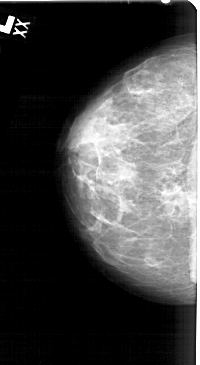

A_1546_1.RIGHT_CC

LEFT_CC LINES 5101 PIXELS_PER_LINE 2791 BITS_PER_PIXEL 12 RESOLUTION 43.5 NON_OVERLAY